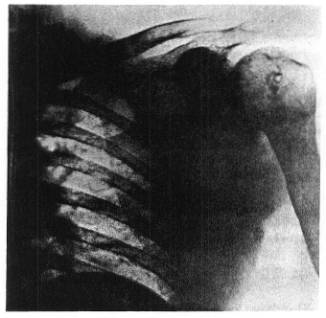

Miss H. P., age 32, Canadian, was treated with the Serial System of Carbonyl groups with free radical terminals in 1927. She had been operated and the microscopic study showed a grade IV malignancy of the carcinoma simplex type. It had infiltrated the axilla and quickly showed renewed activity there and it had also metastasized to the lungs and over to the right supraclavicular space as a good sized (half egg) fixed tumor. The dyspnoea and chest signs showed heavy involvement of the mediastinum and cough was incessant.

Six months after the Treatment, there were no more symptoms or signs of the disease left. The supraclavicular space was clear, and the chest examination indicated the metastases had been absorbed. The photographs made at the time of Treatment and after recovery. In 1955 we heard from her again, that she is in perfect health and no signs of recurrence have appeared.

Miss H. P., before Treatment Miss H. P., after Treatment